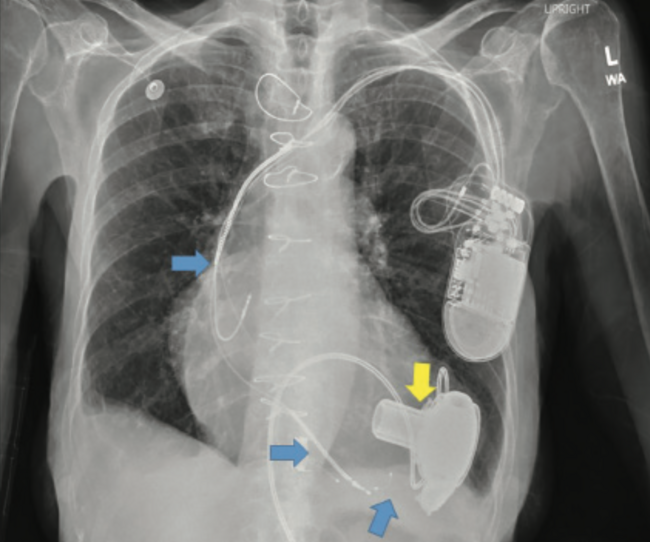

Late Right Heart Failure After Left Ventricular Assist Device Implant: VAD or Valve?

A 76-year-old woman with a history of advanced heart failure and a bi-ventricular pacemaker-defibrillator underwent intra-pericardial left ventricular assist device (LVAD) implant as destination therapy (Figure 1). Pre-implant hemodynamics are shown in Table 1. Echocardiographic right ventricular systolic function at the time was normal and there was only mild tricuspid regurgitation (TR). Three years later, she presented with recurrent hospitalizations for low LVAD flows and bilateral lower extremity edema. Her examination was notable for a prominent C-V wave on jugular venous exam and bilateral, lower extremity pitting edema. A right heart catheterization was performed in order to better characterize the etiology of her decompensation (Table 1). The right atrial pressure tracing was suggestive of severe TR. This was a new finding, and was persistent despite aggressive diuretic therapy and a reduction in device speed (Figure 2). Transesophageal echocardiography confirmed severe TR with incomplete coaptation of primarily the tricuspid valve septal leaflet, secondary to impingement by the implantable cardioverter defibrillator lead (Figure 3). The patient was considered for transcatheter edge-to-edge tricuspid valve repair with lead extraction; however, she declined. In light of that decision, and after completion of intravenous (IV) diuretic therapy, efforts were made to maintain optimization of the right ventricular preload, afterload, and contractility. This was accomplished by use of oral torsemide (which has a better bioavailability than oral furosemide) in addition to scheduled metolazone, ensuring that the pump speed was not excessive to result in interventricular septum bowing leftward with worsening tricuspid valve annular dilatation and TR, and finally by adding digoxin. The use of a phosphodiesterase-5 inhibitor was felt to be of minimal benefit given the absence of significant pulmonary hypertension. As of this time, the readmission rate for volume overload has not been entirely eliminated; however, the frequency has decreased.